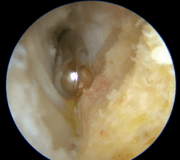

La technique endoscopique

Comme pour la tendinopathie corporéale, l’approche endoscopique permet de réaliser ces gestes par de petites incisions :

- une caméra introduite à l’arrière du talon visualise la zone,

- le chirurgien fraise progressivement la proéminence osseuse,

- il enlève les tissus inflammatoires autour du tendon,

- si nécessaire, il complète par une réinsertion du tendon.